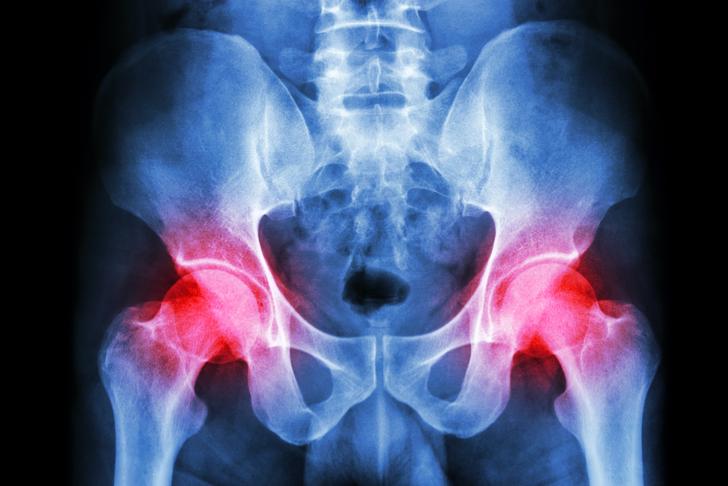

Joint Pain

Joint pain is one of the most common symptoms of rheumatoid arthritis. It is usually a result of inflammation in the joint lining, which can cause swelling, warmth, and tenderness[[1]]. Pain is often worse in the morning or after periods of inactivity.

Joint Swelling

Swelling is another common symptom of RA, as the inflamed joint lining produces excess fluid. This can lead to visibly swollen and tender joints, particularly in the hands, wrists, and knees[[2]].

Joint Stiffness

Stiffness in the joints is a common complaint among those with rheumatoid arthritis. It is often most noticeable in the morning or after periods of inactivity, and can last for several hours[[1]].

Joint Deformity

Over time, the inflammation caused by rheumatoid arthritis can damage the joints and surrounding tissues, leading to joint deformity. This can result in a loss of function and mobility, as well as changes in the appearance of the affected joints[[1]].